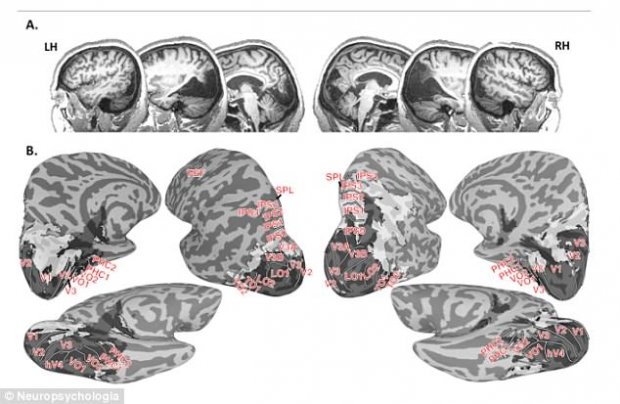

Giáo sư Dutton đưa bà đến Viện nghiên cứu não bộ của Đại học Western ở thành phố London, Canada. Tại đây, các nhà nghiên cứu do Giáo sư Jody Culham phụ trách, đã thực hiện các kiểm tra bao gồm quét MRI để kiểm tra cấu trúc và hoạt động của bộ não bà Canning.

Họ xác định bà mắc một hiện tượng hiếm gặp là hội chứng Riddoch - một dạng mù nhưng người mù vẫn thấy các vật chuyển động, nhưng nếu vật đó đứng yên thì không nhìn được.

Nói về nghiên cứu của mình, Giáo sư Culham cho biết: “Đây là công trình nghiên cứu có lẽ giàu đặc tính nhất từng được tiến hành trên hệ thống thị giác của một bệnh nhân. Bệnh nhân bị thiếu một mẩu mô não có kích thước bằng quả táo ở phía sau não - gần như toàn bộ thùy chẩm, nơi xử lý thị lực“.

“Trong trường hợp của bà Canning, ‘con đường chính’ của hệ thống thị giác gần như bị vô hiệu. Tuy nhiên thay vì làm mất hoàn toàn khả năng nhìn, bà lại phát triển một số ‘đường phụ’ giúp nhìn những vât đang chuyển động và được gửi tới xử lý ở các phần khác của não”.

Về bản chất, bộ não của bà Canning đang phát triển những đường vòng bất ngờ, độc đáo quanh con đường bị hư hại.

Trong nghiên cứu được công bố trên tạp chí y khoa Neuropscyhologia, bà Canning đã có thể nhận ra chuyển động, hướng, kích cỡ và tốc độ quả bóng lăn về phía mình. Bà cũng có thể dùng tay để mở, chặn và lấy chúng đúng lúc. Bà có thể di chuyển xung quanh ghế.